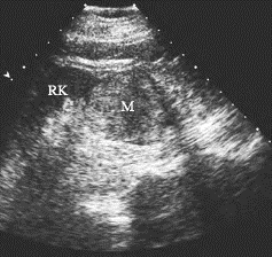

图29-10 肾盂癌声像图

注:左肾肾盂内不规则低回声包块(M)